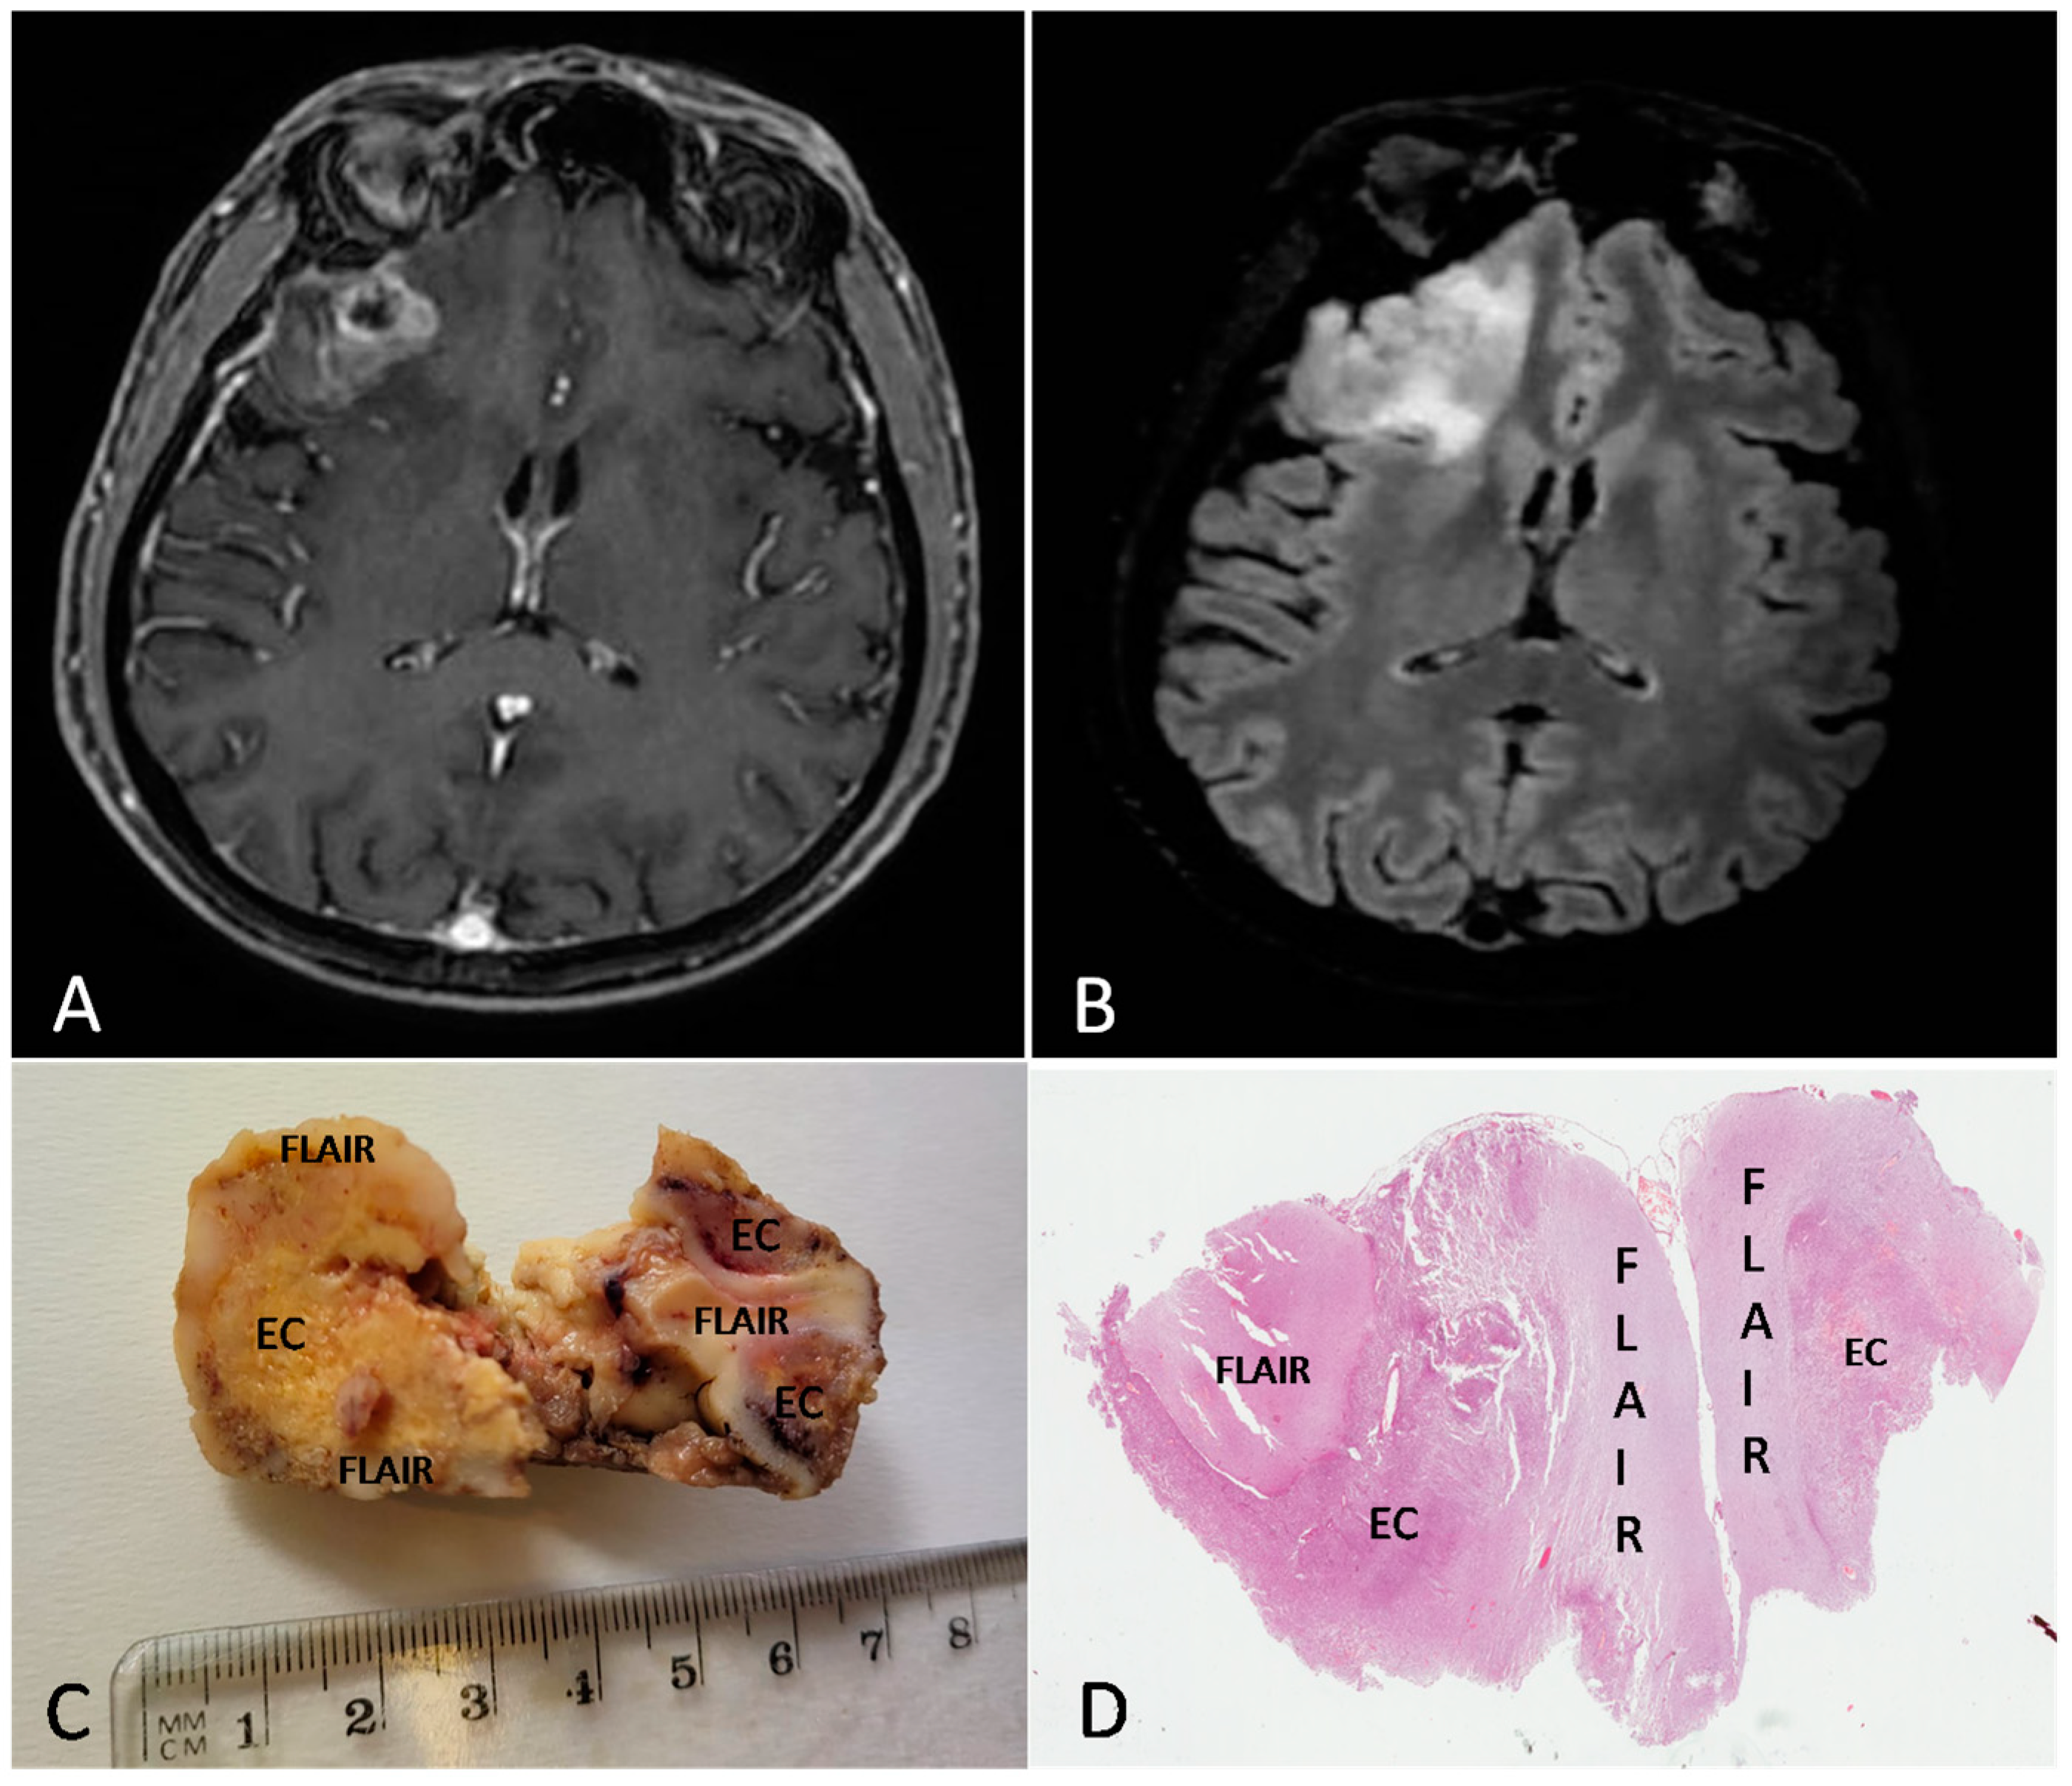

Figure 2 and Figure 3 show the MRI features, the gross findings and the histopathology of two cases from our series.

Figure 2.

Preoperative MRI from a 57-year-old man. (A) Axial section of a T1w sequence with gadolinium showing a left frontal tumor with necrotic core and ring enhancement. (B) FLAIR sequence showing a hyperintensity beyond the EC. (C,D) Gross image (C) and histologic low magnification (D) showing both EC and FLAIR region from the excised mass ((D) H&E; original magnification 25×).